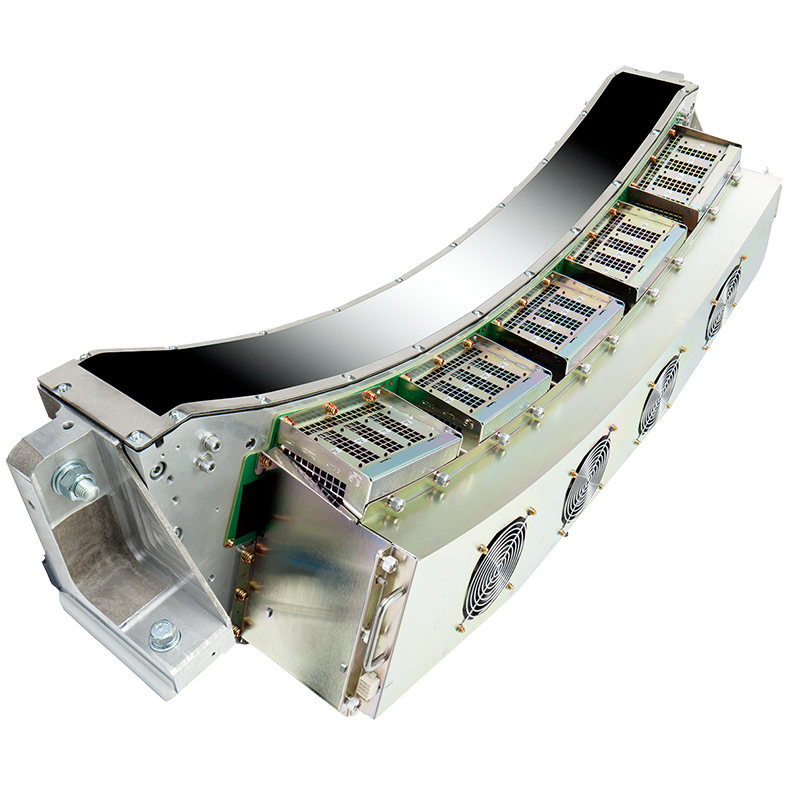

Детектор PUREViSION

Новый детектор PUREViSION обеспечивает снижение лучевой нагрузки и визуализацию с низким кВ, что позволяет врачам не беспокоиться об оптимизации протоколов облучения и сделать КТ-исследования еще более безопасными для всех пациентов. Внедрение передовых разработок в производственные процессы и систему сбора данных позволило создать детектор с увеличенным на 40% световым выходом и минимальным шумом, что сделало PUREViSION одним из самых эффективных детекторов, существующих в отрасли, и по-прежнему единственным детектором с истинным разрешением 0,5 мм.